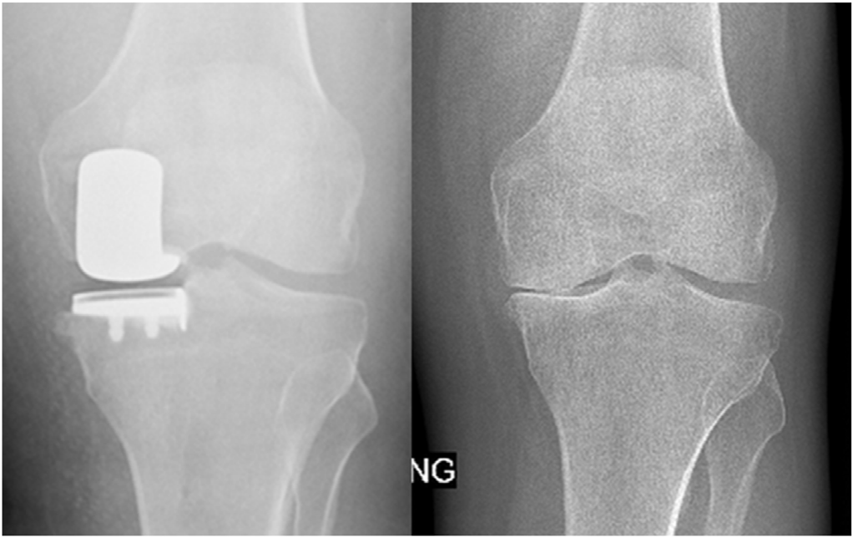

X-Ray:右膝内侧间隙明显狭窄,站立位内侧间隙消失,外侧间隙正常,膝关节稳定。

诊断:右膝关节内侧间室OA。